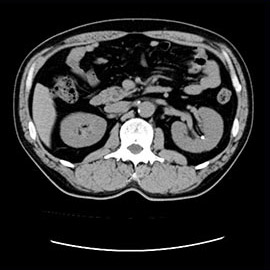

80列マルチスライスCTで撮影した画像

腹部

腹部(造影)